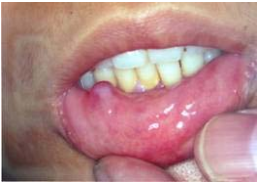

32. 依下圖,15歲少年訴稱下唇有腫塊存在一個多月,沒有長大趨勢,無痛。下列何診斷最合理?

(A)乳突瘤 (B)肉芽腫 (C)脂肪瘤 (D)黏液囊腫